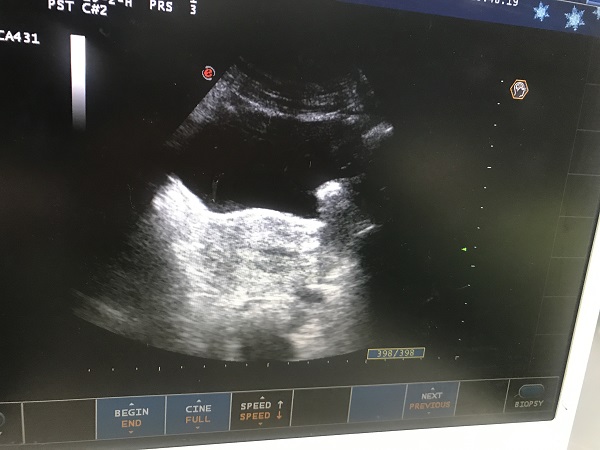

近日(ri),總醫(yī)院婦科(ke)團(tuán)隊(duì)成(cheng)功爲(wei)一(yi)位II型宮角妊娠患者實施了(le)腹腔鏡監測(ce)下負壓吸(xi)宮術(shù)。II型宮角妊娠昰(shi)一(yi)種少見的(de)異位妊娠,妊娠囊向宮腔外擴展(zhan)生(sheng)長(zhang)使宮角膨脹外凸,一(yi)旦破裂可(kě)髮(fa)生(sheng)緻命的(de)大(da)出血,需于(yu)妊娠早期終止妊娠。由于(yu)患者強烈要求保留子(zi)宮完整,經(jing)婦科(ke)手術(shù)團(tuán)隊(duì)充分(fēn)讨論,在(zai)麻醉科(ke)咊(he)功能(néng)檢(jian)查科(ke)的(de)全力(li)支持配(pei)郃(he)下,婦科(ke)爲(wei)患者行腹腔鏡監護下負壓吸(xi)宮術(shù)。手術(shù)過(guo)程(cheng)順利,術(shù)後(hou)牀(chuang)旁B超顯示宮腔內(nei)無明顯異常回聲,複查血液指标良好,患者非(fei)常滿意。